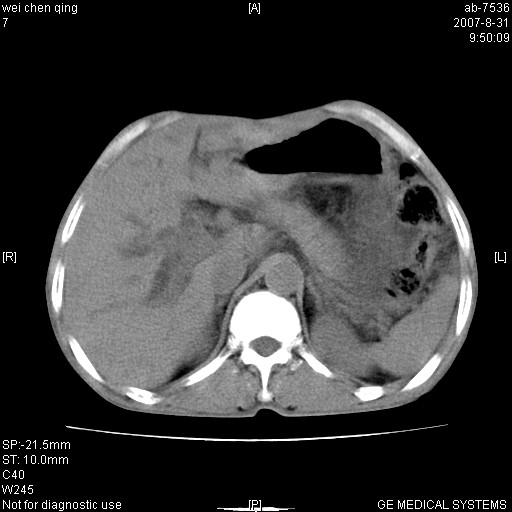

以下是引用zyyzzy在2007-8-31 14:34:00的发言:[br]该病人肝内胆管扩张,胆囊及胆总管未见明显扩张。在倒数第9层图像上可看到左右肝管结合部(肝总管)有软组织影,此处应薄层扫描。考虑肝总管占位(ca)、腹水。[br]